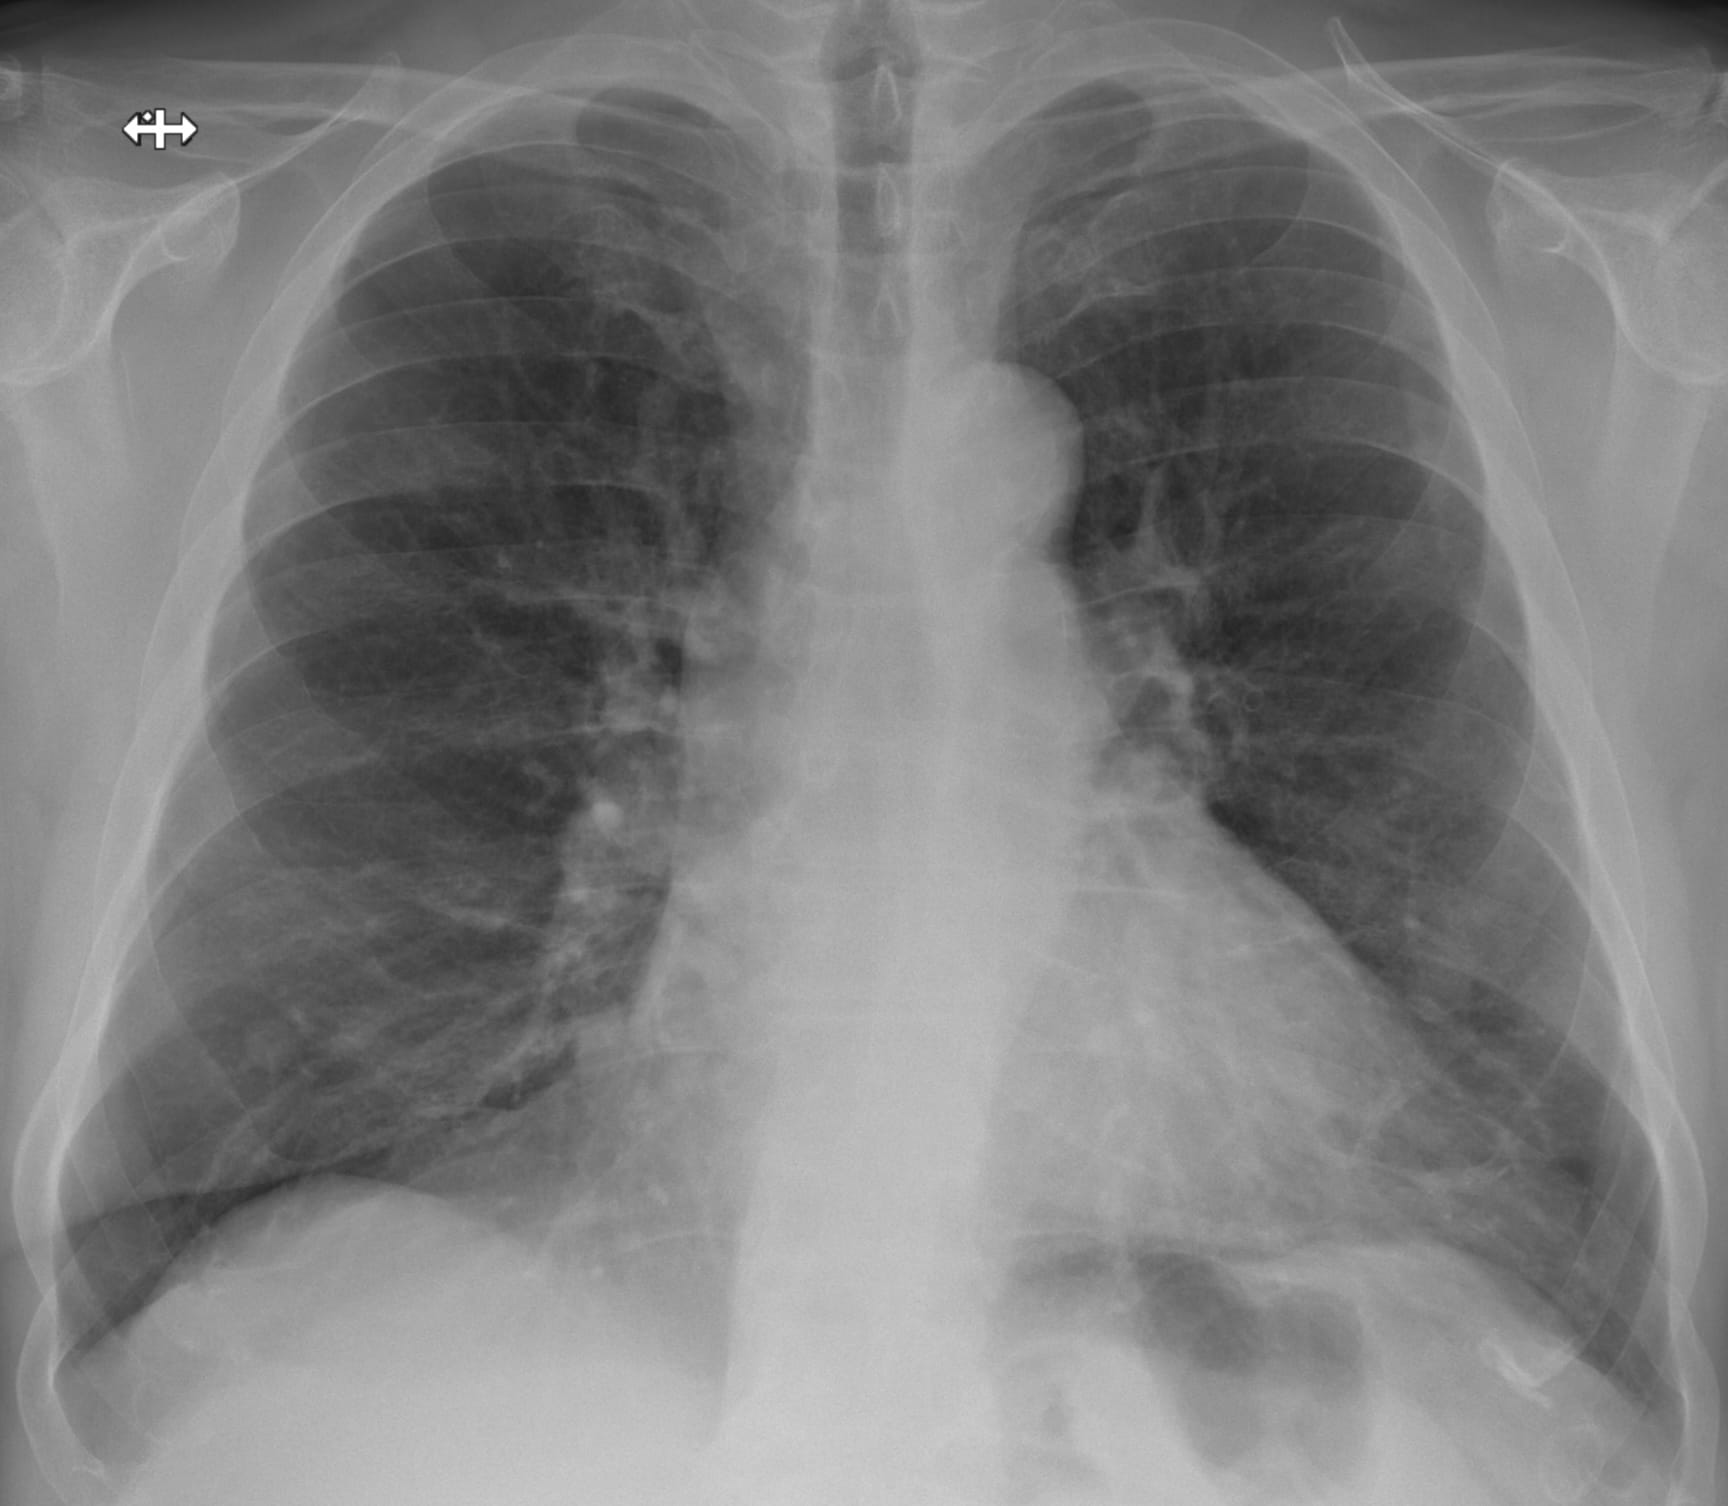

Airway-dominant phenotype

Emphysema-dominant phenotype

Mixed phenotype

We can make these distinctions on CT.

Note: bronchial wall thickening